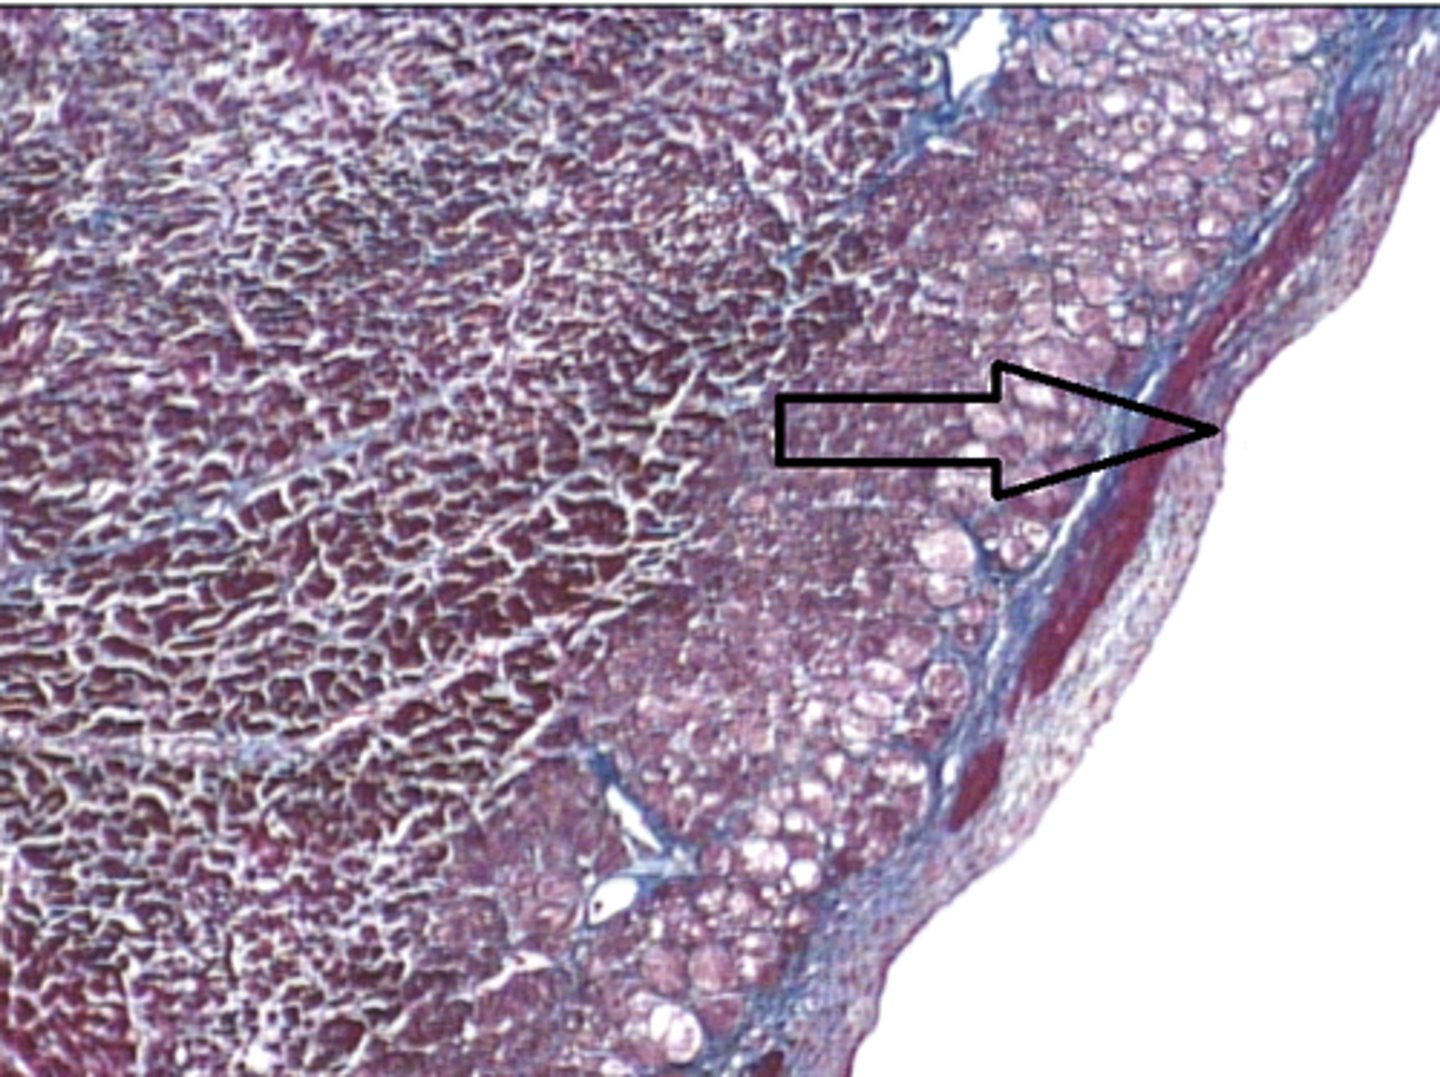

spleen

where is this tissue located?

capsule

C?

Trabeculae

T?

white pulp

W?

red pulp

R?

WBCs

20% of spleen

What does white pulp contain? What percentage of spleen is it?

(nuclei are basophilic)

is white pulp or red pulp darker staining (basophilic)?